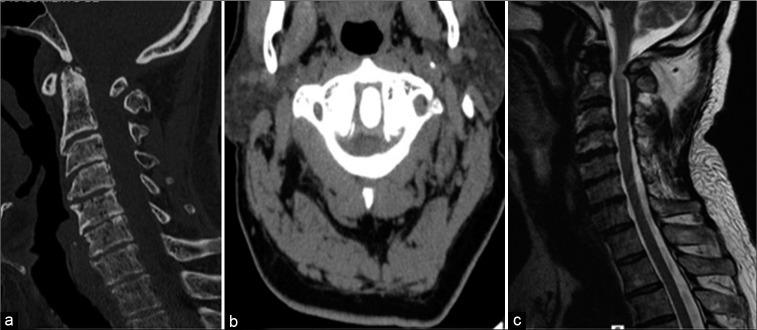

A 54-year-old male presented with the sudden onset of a severe quadriparesis and loss of proprioception after a minor fall. The magnetic resonance (MR) scan showed cord compression at the C1 level attributed to C1 arch hypoplasia. Two months following a decompressive C1 laminectomy without fusion, and the patient was symptom free.

Posterior C1 arch hypoplasia is a rare anomaly that can contribute to cervical cord compression and myelopathy. The optimal surgical management may include, as in this case, a posterior decompression without fusion.